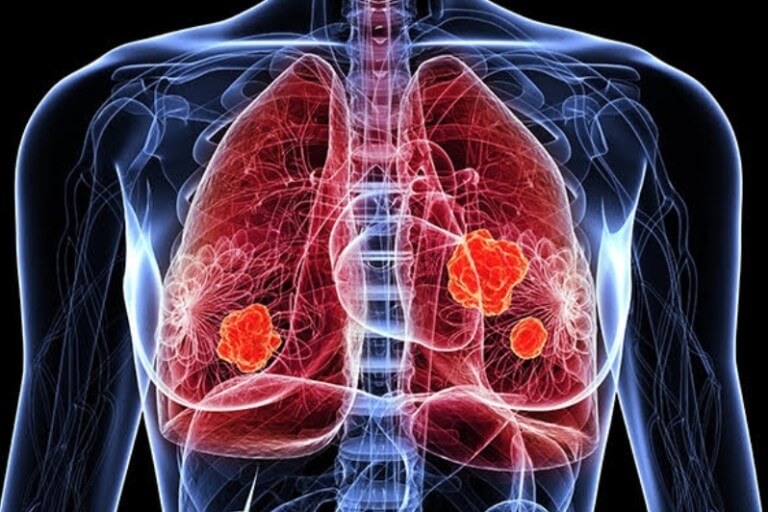

만성 폐 질환이나 결핵, 암 등으로 인해 발생할 수도 있고, 유전적 요인으로 인하여 발생할 수도 있습니다.